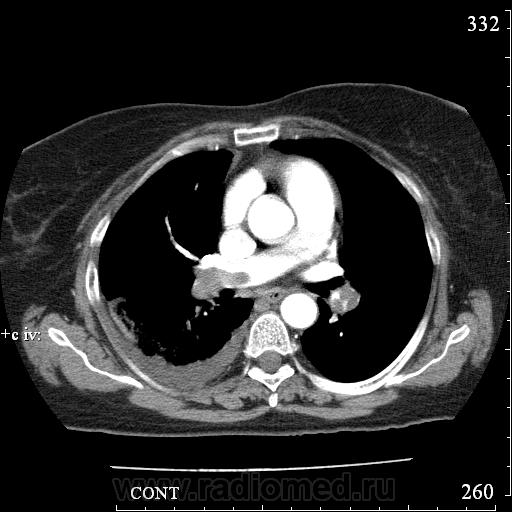

Еще один случай диагностики ТЭЛА методом КТ-ангиографии у женщины 59 лет. Основная клиническая жалоба - выраженная одышка. Определяется: полный дефект наполнения в системе правой ЛА (бифукация и нижнедолевая), неполный дефект наполнения в левой ЛА (нижнедолевая), пристеночные тромбы по задней стенке в области бифуркации обеих легочных артерий. Инфаркт (массивное кровоизлияние) нижней доли правого легкого. Правосторонний малый (120см3) гидроторакс. Несмотря на выраженные тромбы, поперечники легочных артерий - в пределах нормы.; на нативной (безконтрастной) КТ - тромбы не видны. Несмотря на почти полный дефект наполнения в левой нижнедолевой артерии, изменений в легочной ткани левого легкого нет. Также приводится топограмма, как вариант, приближенный к рутинной рентгенограмме